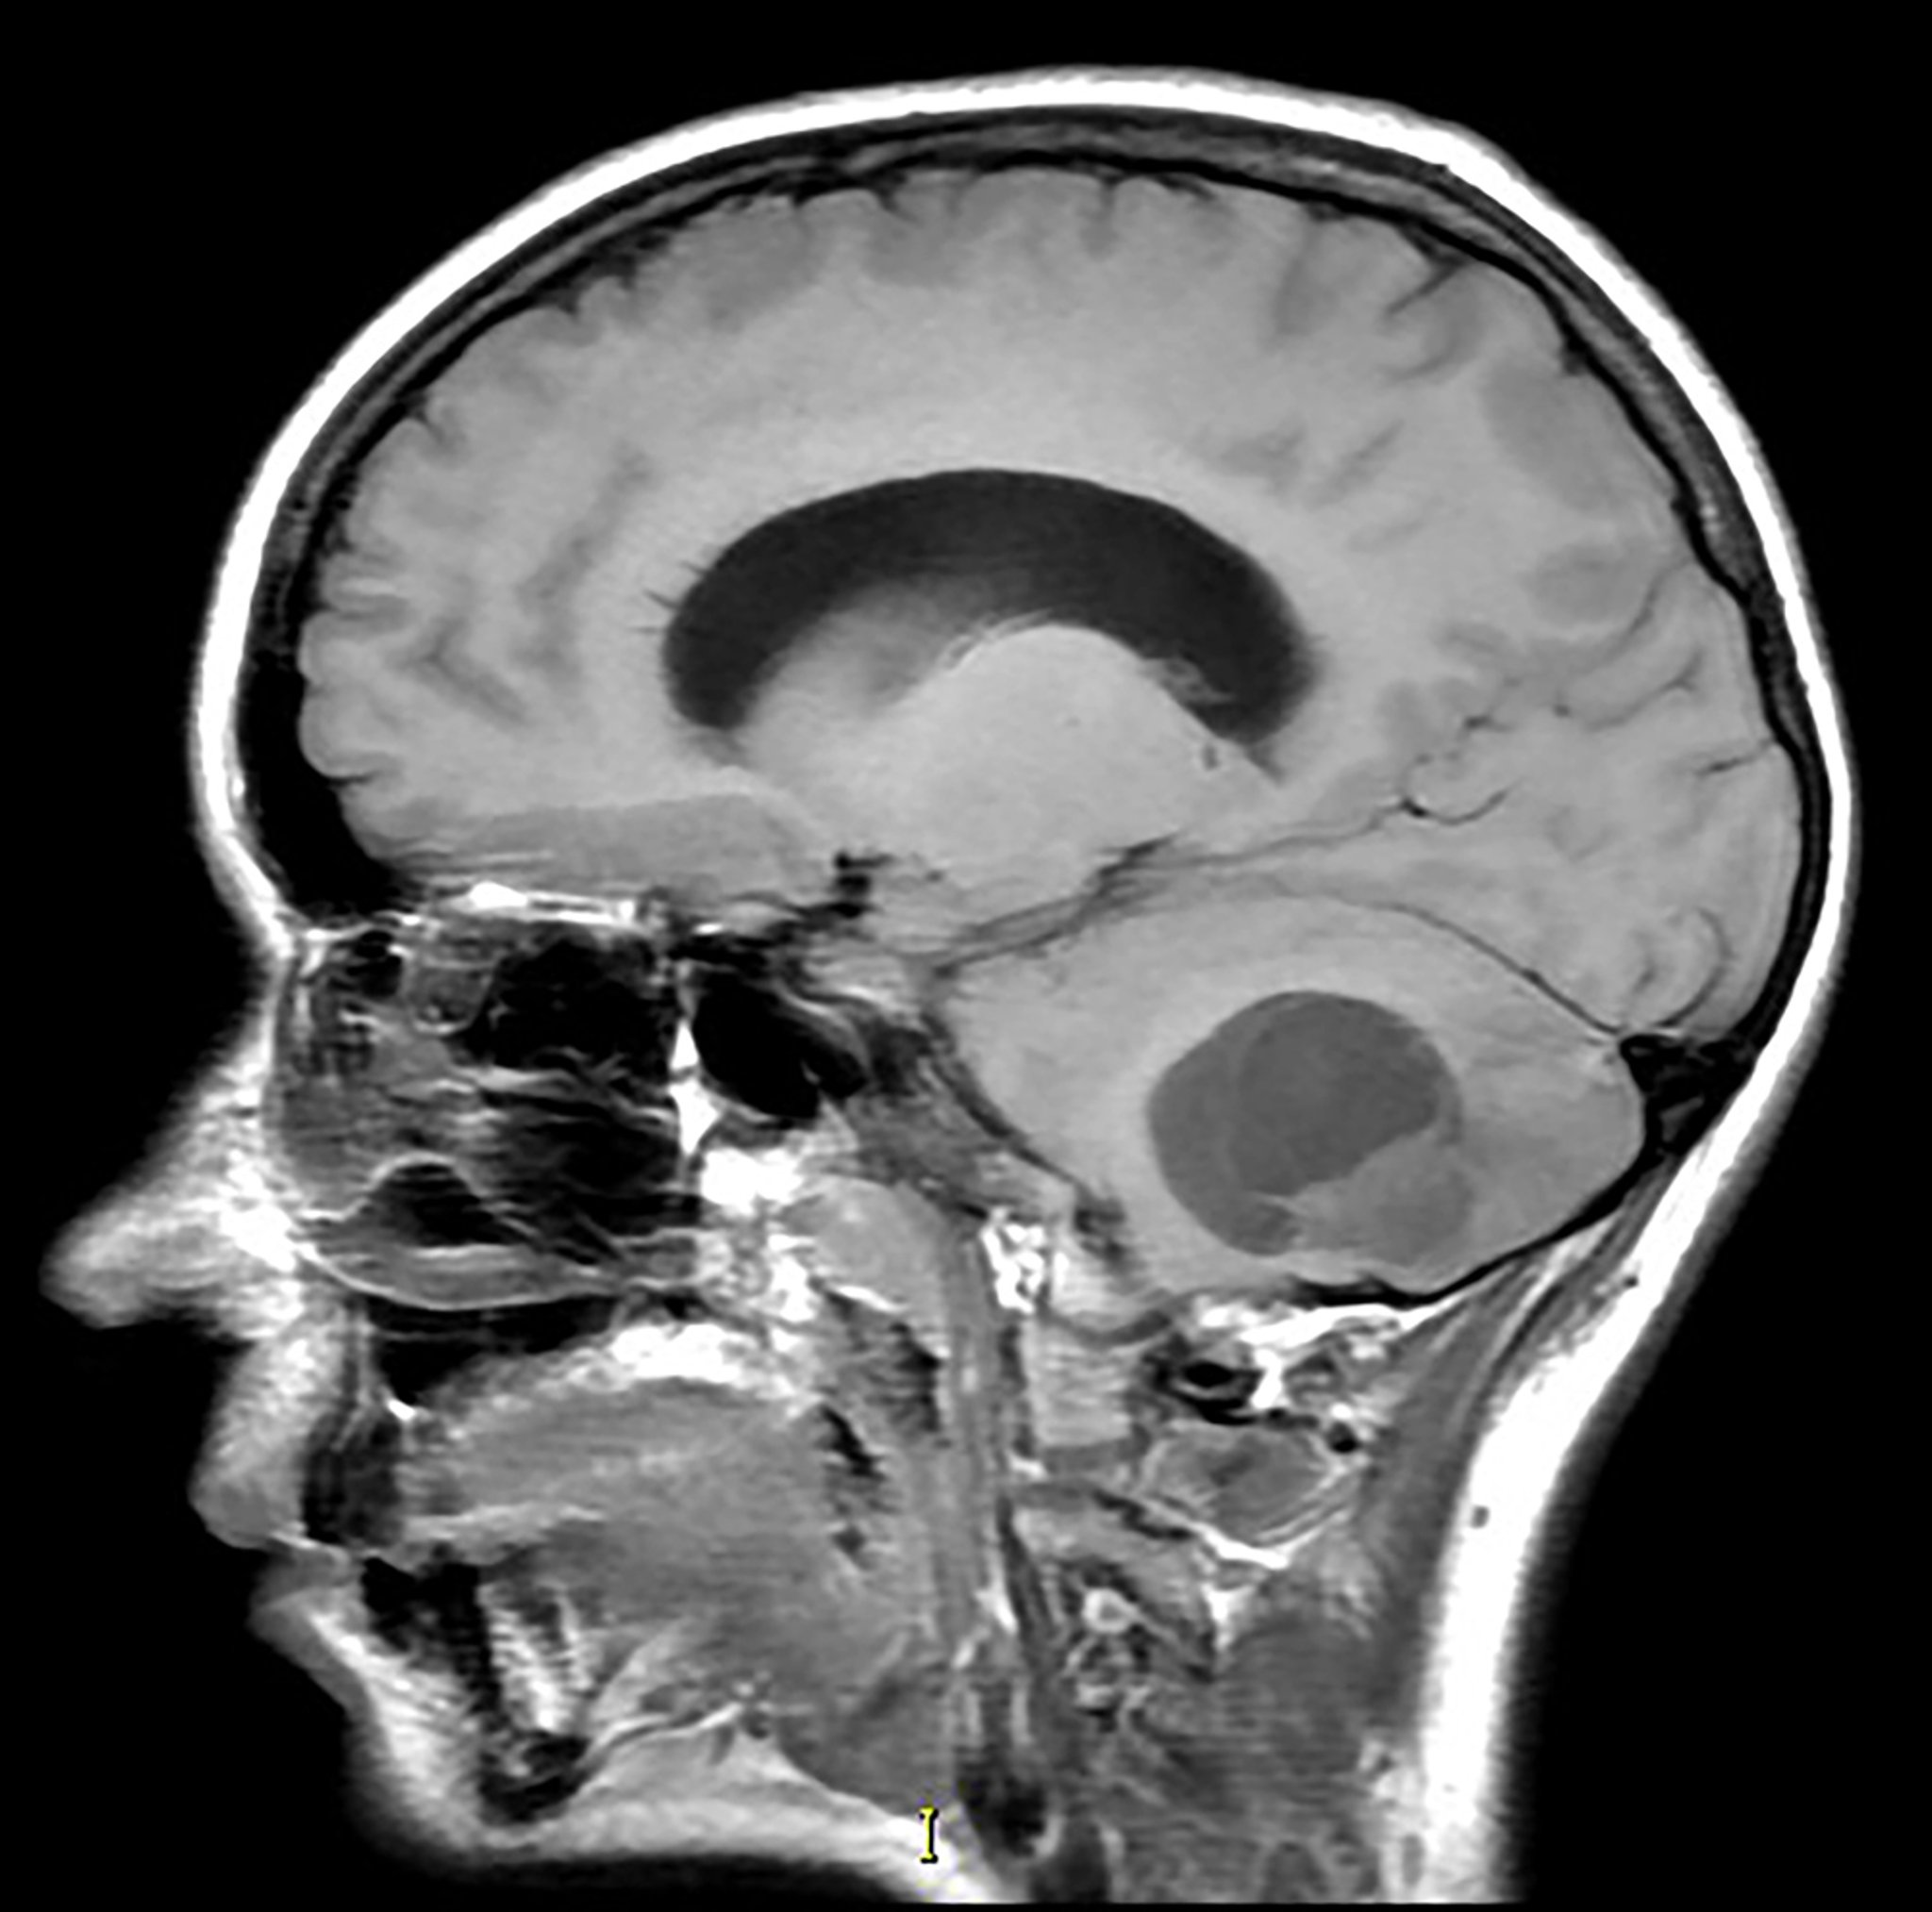

Emangioblastoma cerebellare (RM)

Questa immagine RM sagittale, pesata in T1, senza contrasto mostra una massa parzialmente cistica e solida nel cervelletto inferiore con effetto massa associato. Questo è l'aspetto più comune di un emangioblastoma. Questo tumore è visibile con maggiore frequenza nei pazienti con sindrome di von Hippel-Lindau.